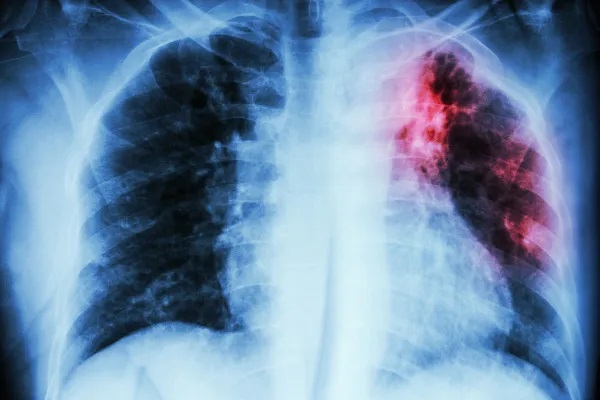

Manaus registrou 1.508 novos casos de tuberculose este ano, até o momento. Segundo a Secretaria Municipal de Saúde (Semsa), 41% dos registros foram na faixa etária de 20 a 39 anos.

A forma clínica pulmonar representa 1.287 do total de casos.

A tuberculose é uma doença infecciosa e transmissível, causada pela micobactéria Mycobacterium tuberculosis ou Bacilo de Koch (BK), que afeta prioritariamente os pulmões. O principal sintoma é a tosse e, por isso, a recomendação é para que pessoas com tosse por duas semanas ou mais sejam examinadas, procurando uma das Unidades de Saúde da rede municipal para a realização de exames.